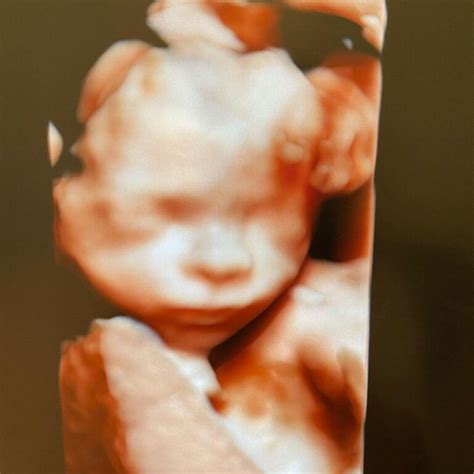

Morfologiile fetale sunt investigații de natură imagistică (ecografii) realizate de specialiști, care au scopul de a monitoriza evoluția sarcinii și de a certifica dezvoltarea normală a fătului.

Ecografia de morfologie fetală trimestrul 2 se recomandă între săptămânile 16-20, deoarece în această perioadă pot fi vizualizate organele fătului, acestea fiind optim dezvoltate.

În perioada aceasta, poziția în uter permite vizualizarea eficientă a structurilor și parametrilor care ar putea indica dacă fătul suferă de un anumit tip de malformație.

Rezultatele ecografiei de morfologie fetală trimestrul 2 permit depistarea cu acuratețe a diferitelor tipuri de anomalii care pot interesa peretele abdominal sau absenta encefalului.

Ecografia de morfologie fetală trimestrul 2 reprezintă o etapă importantă în sarcină, întrucât în acest moment poate fi aflat cu precizie, la solicitarea părinților, și sexul copilului.